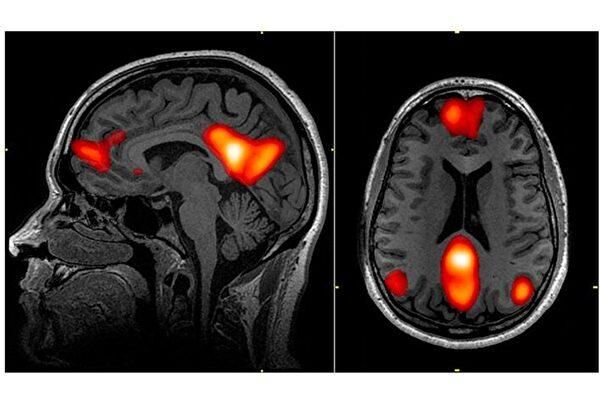

研究者让受试者欣赏画作、建筑或自然风光的图片,并用功能性磁振成像(fMRI)监控受试者脑部的活动。结果显示,受试者的大脑视觉区域对于不同类别的美图,产生的信号各不相同。然而在大脑中一个被称为“预设模式网络”(DMN,Default Mode Network)的功能性区域,却对所有类型的美图有着一致的脑部活动模式。

研究负责人、德国马克斯普朗克经验美学研究所(Max Planck Institute for Empirical Aesthetics)的爱德华.凡赛尔(Edward Vessel)说,“我们不知道这种一致性是否是经过‘预设模式网络’自行处理后的结果,但此网络显然能够获取关于美感的某种抽象又普适的规则。”

新的研究发现,这个网络在人们的审美、或被视觉艺术感动的体验中起着重要作用。研究者称,由于此网络当人与外在世界互动时处于休眠状态,因此视觉的美感体验信息出现在这个区域着实不同寻常。